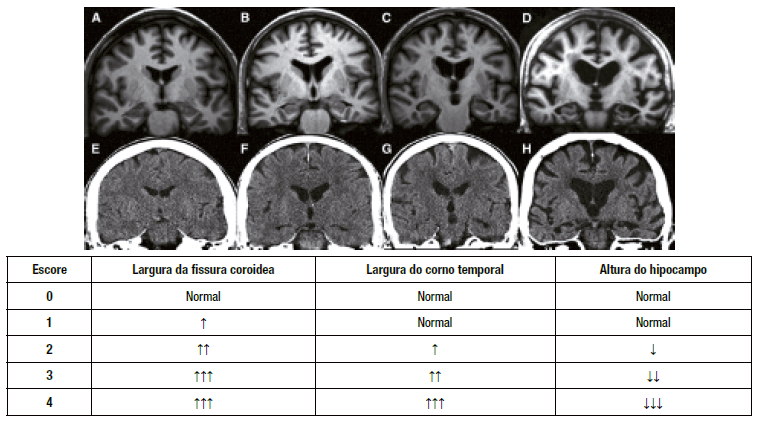

Referência Visual — Graus MTA (0–4)

Referência visual Escala MTA — graus 0 a 4

Grau Denominação Características

0 Normal Sem atrofia. Fissura coroídea, hipocampo e corno temporal normais.

1 Leve Alargamento mínimo da fissura coroídea e/ou do corno temporal. Hipocampo em volume normal.

2 Moderada Alargamento da fissura coroídea e do corno temporal. Redução leve do hipocampo (≤ 25%).

3 Grave Alargamento importante do corno temporal. Redução moderada do hipocampo (26–50%).

4 Severa Alargamento máximo do corno temporal. Redução grave do hipocampo (> 50%).